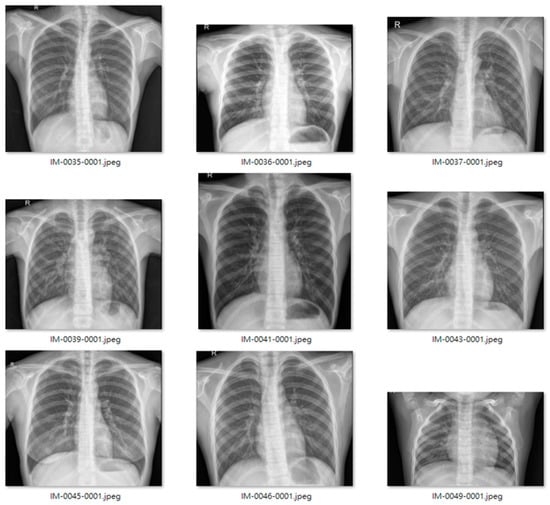

We used an open-source dataset provided by the Kaggle data science competition platform for training (https://www.kaggle.com/paultimothymooney/chest-xray-pneumonia accessed on 25 March 2018) [31]. The dataset comprised thoracic cavity images from child patients (1 to 5 years old) from the Guangzhou Women and Children’s Medical Center, China. These images were classified by two expert physicians and separated into training, test and validation sets. Figure 8 displays the dataset structure, with training sets including 1341 and 3875, test sets 234 and 390, validation set 8, and eight normal and pneumonia images, respectively. Figure 9 and Figure 10 show examples of normal and pneumonia thoracic cavity X-ray images, respectively.

Figure 9. Example normal thoracic cavity X-ray images from the study dataset [31].